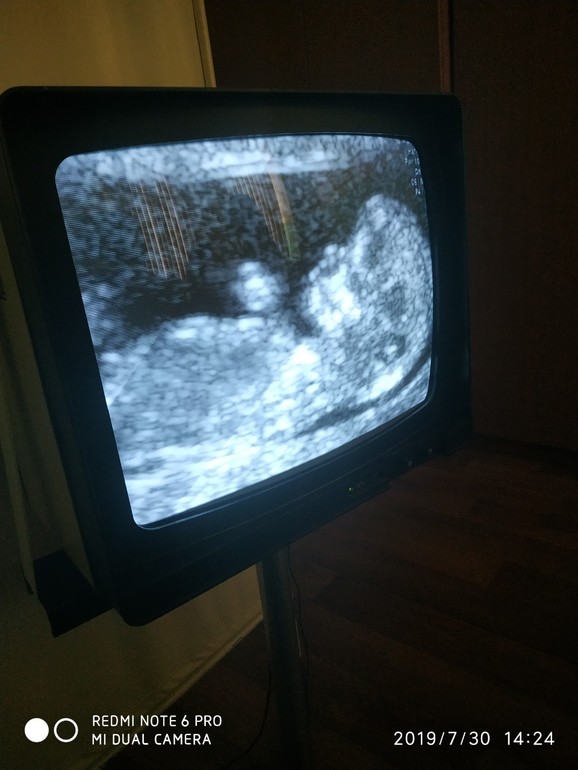

12 неделек. Первый скрининг🤗 Угадываем пол малыша

Сходили мы с мужем на первый скрининг, увидели наше четвертое счастье.

Наши параметры:

Ктр 56.7

Чсс 169

Толщина воротн.простр. 1.3мм

Носовая кость или 1 или + не понятно

Хорион по передней стенке

Срок по мс 12 и 0. По узи 12 и 2.

Все хорошо) Пороков развития не выявлено)

Иииии.... самое интересное - фото. Может у вас есть предположения по поводу пола.

Ничего не видно, на первом фото только головка, а на втором очень далеко.